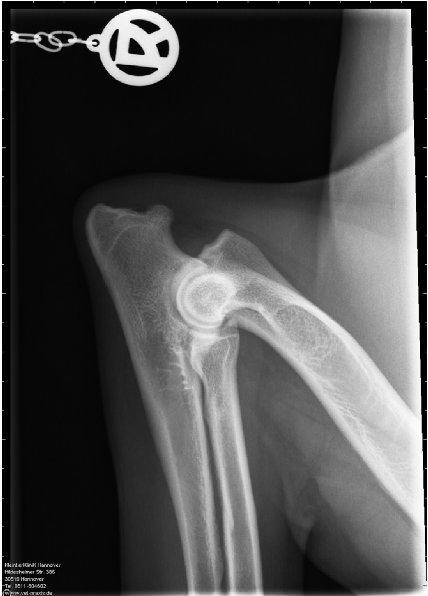

ED - OCD - Röntgenaufnahme